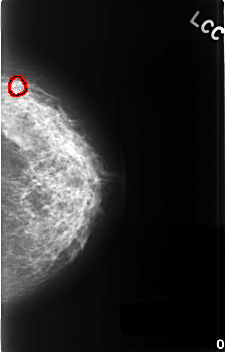

FILE: C_0341_1.LEFT_CC.OVERLAY

TOTAL_ABNORMALITIES 1

ABNORMALITY 1

LESION_TYPE CALCIFICATION TYPE DYSTROPHIC DISTRIBUTION CLUSTERED

ASSESSMENT 2

SUBTLETY 5

PATHOLOGY BENIGN_WITHOUT_CALLBACK

TOTAL_OUTLINES 1

BOUNDARY